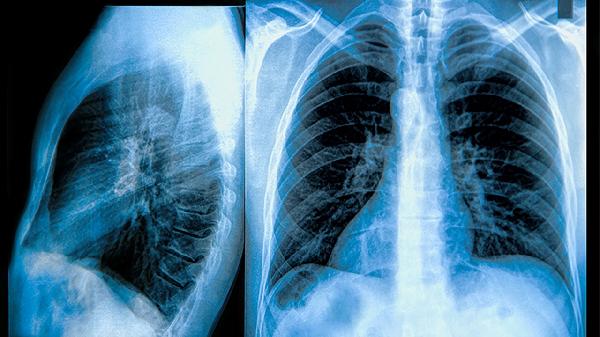

清肺散结丸主要用于治疗肺结节、肺结核等肺部疾病,具有化痰止咳、活血止痛、清热解毒等功效。

清肺散结丸可用于治疗肺结节。肺结节可能与长期吸烟、空气污染、肺部感染等因素有关,通常表现为咳嗽、胸痛、痰中带血等症状。患者需遵医嘱使用清肺散结丸、小金丸或夏枯草颗粒等药物,同时定期复查肺部CT,监测结节变化。

清肺散结丸适用于肺结核辅助治疗。肺结核主要由结核分枝杆菌感染引起,常见症状包括低热、盗汗、消瘦、咳嗽咳痰等。患者需联合使用异烟肼片、利福平胶囊等抗结核药物,同时配合清肺散结丸改善症状,治疗期间需注意隔离防护。

清肺散结丸可用于肺部肿瘤的辅助治疗。肺部肿瘤可能与遗传、放射性物质接触有关,常见症状为咯血、呼吸困难、持续胸痛等。患者需在医生指导下配合使用清肺散结丸、平消胶囊等药物,同时根据病情选择手术、放疗或化疗等治疗方案。